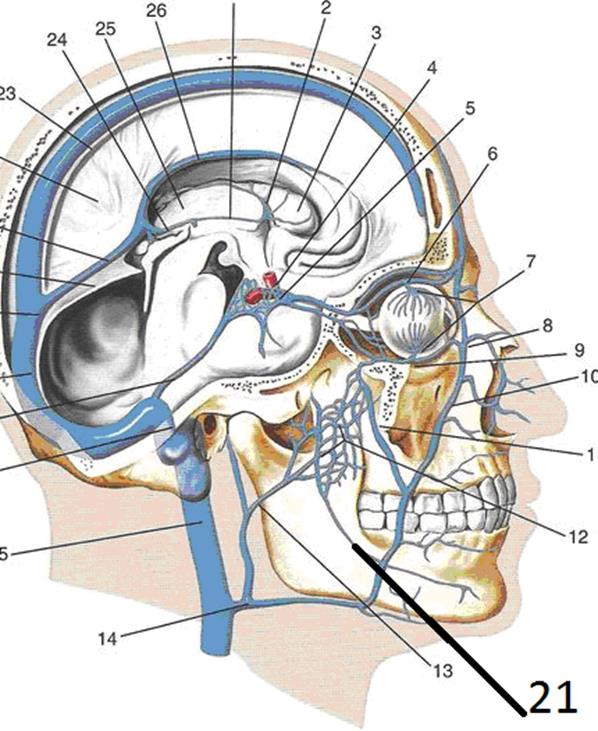

Анатомия внутренней яремной вены: КТ изображения